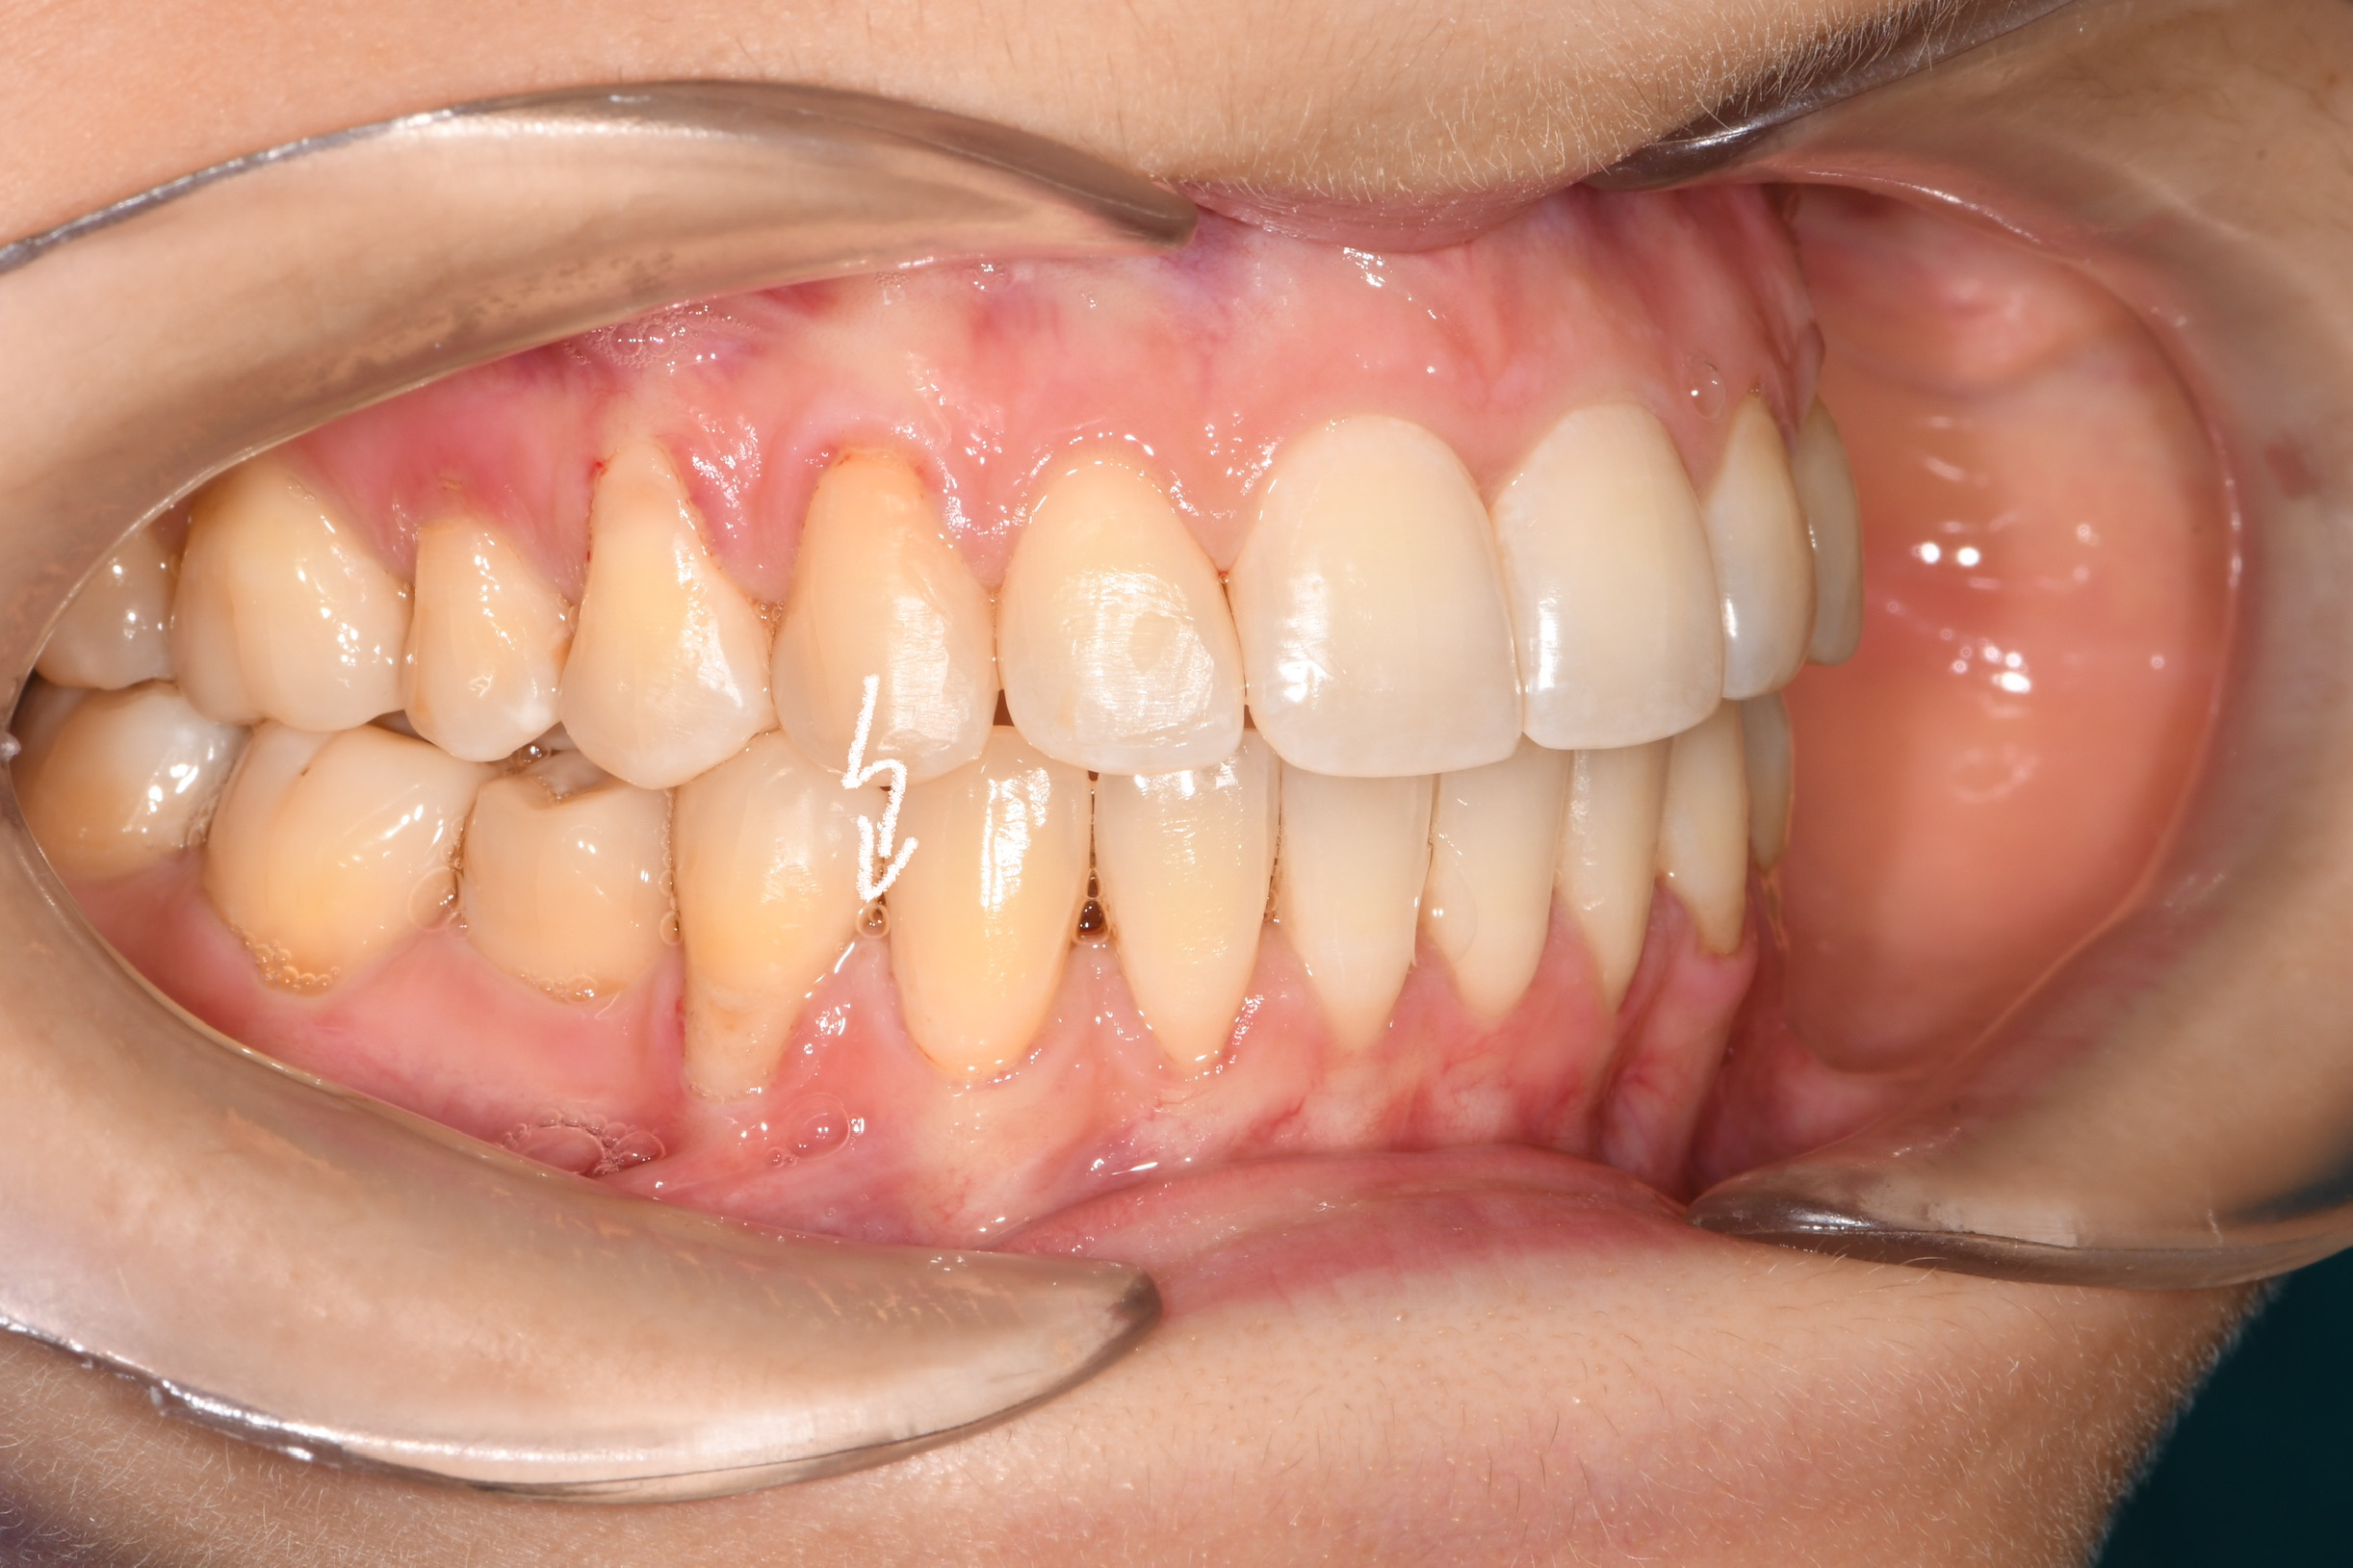

Az elmúlt évekből rengeteg szakmai referenciát tudnánk bemutatni, amelyek különböző fogszabályozási problémákat oldottak meg. Válogatva a több száz esetből, ezen az oldalon olyan képeket, információkat igyekeztünk bemutatni, amelyeknek a segítségével a jövőbeni pácienseinknek azt tudjuk üzenni: A Te fogsorod is lehet gyönyörű!

(Képeket a Pácienseink külön írásos beleegyezésével mutatjuk be!)